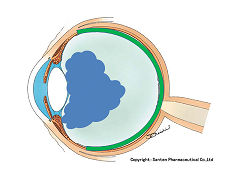

マリオット盲点以外の部位が欠ける場合は病気となるのですが、視野が欠ける代表的な疾患として、緑内障があります(日本人の失明の原因の第一位)。

マリオット盲点を認識しづらいのと同様に、実は、緑内障で視野が欠けた場合も初期の段階では気が付きにくいのです。(初めて病院に来る時には、末期だったんてことがよくあります。)